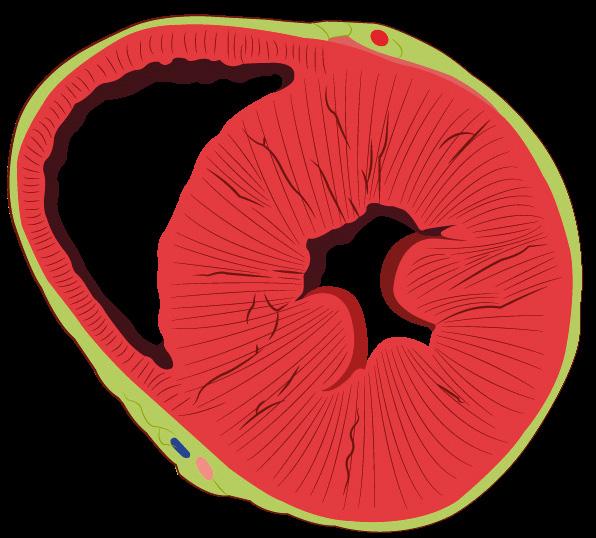

La obstrucción completa de la arteria provoca una elevación del segmento ST cóncava hacia abajo en derivaciones contiguas (> 1 mm en todas las derivaciones) . Por tanto, la localización del infarto se determina por las derivaciones, en las cuales se eleva el segmento ST:

Septal (obstrucción de ADA): V1-V2.

Anterior, incluido el ápex (obstrucción de ADA distal): V3-V4.

Lateral (obstrucción de arteria circunfleja): I, aVL (lateral alto) . V5-V6. (lateral bajo)

Anterior extenso (obstrucción de ADA proximal): V1-V6

Inferior o diafragmática (obstrucción de ADP, rama coronaria derecha): II, III aVF